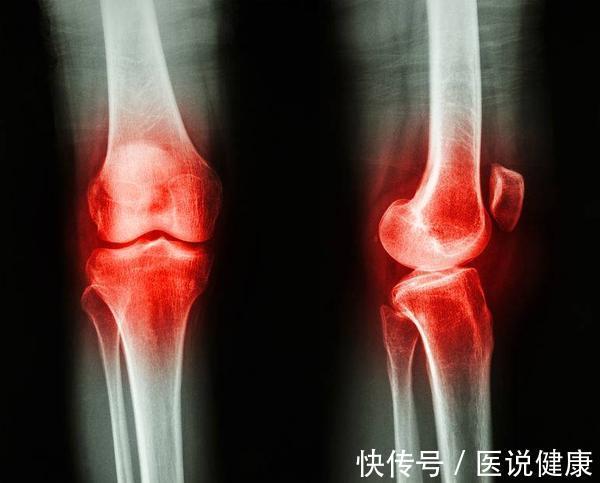

文章插图

我们都知道,痛风和关节炎的发病位置都在关节处,发病症状也有一些相似,所以大部分人很难区分痛风和关节炎。

关节炎的类型比较多,而痛风就是其中一种。因为痛风和关节炎的治疗有很大区别,所以如何区分关节炎和痛风就成了大家最关心的问题。